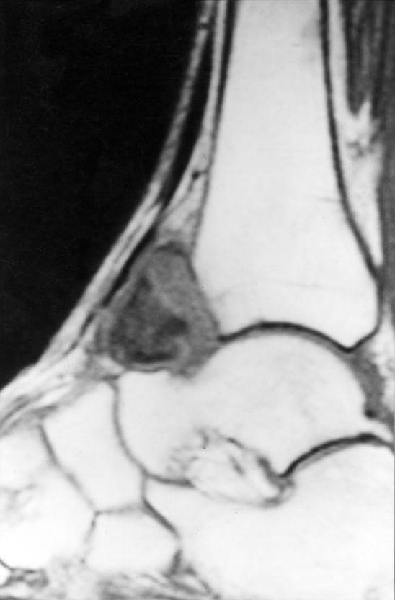

剥脱性骨软骨炎

王会余 男  65岁

软骨剥脱